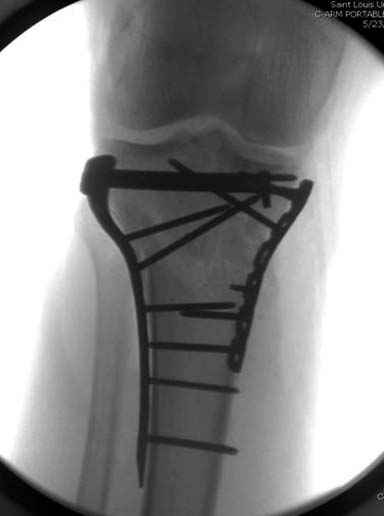

На вашем место я бы подождал с фиксацией до готовности кожных покровов, и за это время можно было подобрать соответствующий фиксатор, т.е более длинная пластина снаружи и медиальная пластина на апексе перелома как подпорка. Здесь приемлем как раз минимальный доступ.

Имеющаяся импрессия не потребовала пластики - достаточным оказалось поднять отломок

Если там действительная импрессия, пустое место без структуральных заполнителей, кость или синтетические материалы, не восстановится, а образуется коллапс, и ось конечности поведет после нагрузки. Кроме того там возможно "болт стяжка"?, в медиальной стороне выступает за кортекс, можно было укоротить! Потом создается впечатление, что не соответствуют мыщелки большеберцовой и бедренной костей? Покажите снимок.

Здесь пару случаев для сравнения,...в первых 1-4 слайдах метод фиксации одним фиксатором, как видно после 8 месяцев сохранилась ось. С 5 по 9 вариант двумя пластинами...